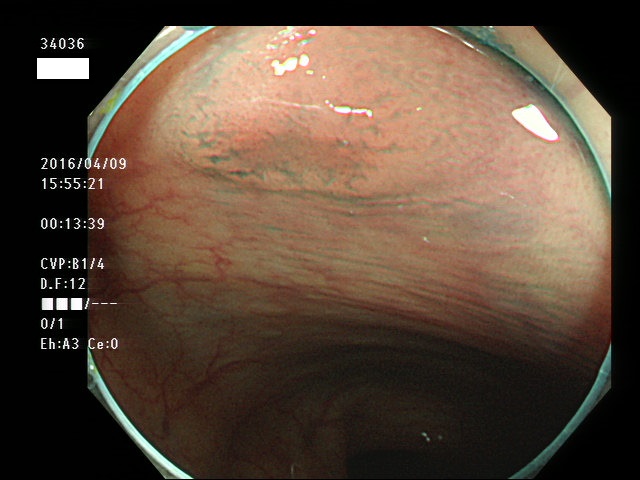

上記100名より抽出した平坦・陥凹型腺腫(=癌化の危険が高いが見落としやすい病変)の内視鏡写真